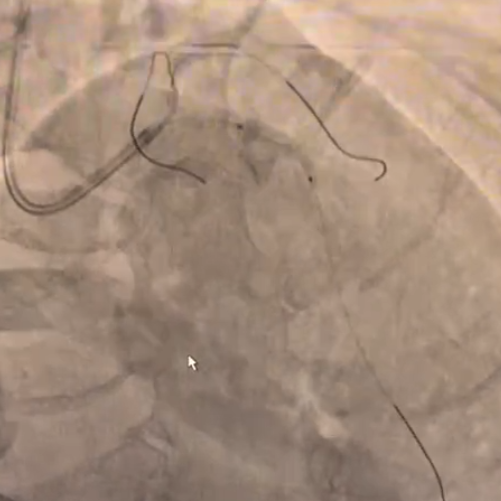

简要病史:患者既往因稳定性心绞痛,于2025年4月入院行CAG+PCI 治疗。RCA近中段“旋磨+冲击波”处理后植入4枚支架。本次入院计划处理LCX。

支架植入:在IVUS引导下,于OM2-LCX远端精准植入2.5×38mm药物支架,经非顺应性球囊后扩,术后造影及腔内影像确认支架贴壁理想,无边缘夹层及壁内血肿,TIMI血流3级。

OM1病变处理:球囊扩张后于OM1病变处植入1枚支架并进行支架内后扩,复查造影提示支架贴壁良好,未见夹层、血肿。